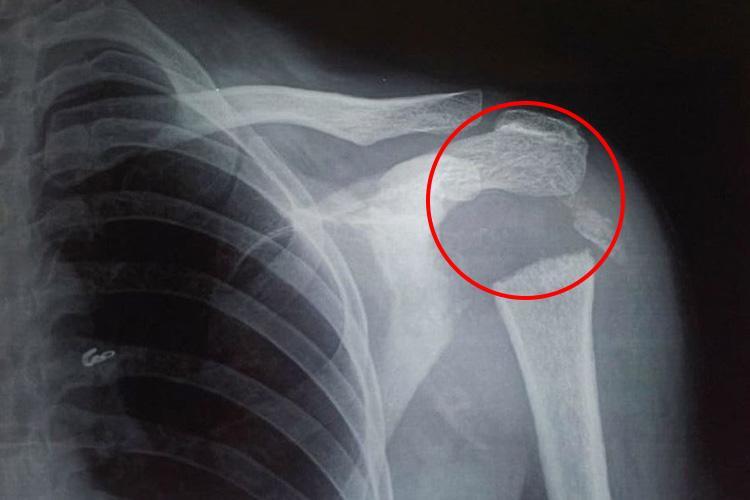

Sau khi tiến hành chụp chiếu, tia X cho thấy phần xương tròn kết nối cánh tay với vai của cô đã tiêu biến khiến nó chỉ còn một mảnh nhỏ. Các bác sĩ tại Viện Khoa học Y khoa Pondicherry ở Ấn Độ đã cho xét nghiệm nhiễm trùng, nội tiết tố cũng như trao đổi chất, tuy nhiên mọi thứ đều ở trạng thái bình thường.

Theo báo cáo trường hợp của Tạp chí Y khoa Anh, vùng xương dài ở cánh tay trên của người phụ nữ đã biến mất. Ban đầu, đội ngũ y bác sĩ nghi ngờ do bệnh về thần kinh gây ra nhưng cô hoàn toàn không hề có triệu chứng liên quan. Sự thiếu hụt các triệu chứng thần kinh khiến gây ức chế cho cơ thể, do vậy các bác sỹ chẩn đoán cô mắc chứng Gorham-Stout, một căn bệnh cực kỳ hiếm gặp khiến xương tiêu biến.